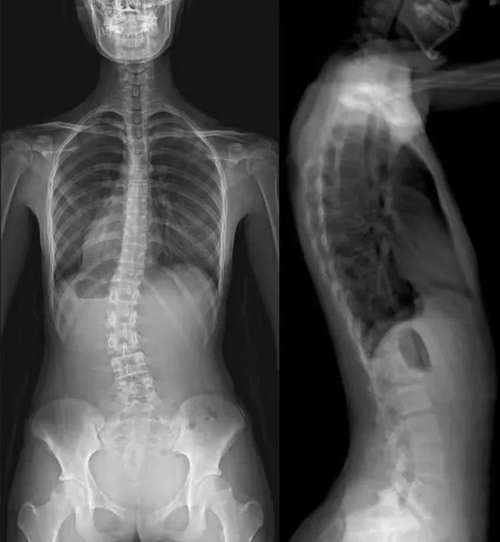

应用适应症:全脊柱摄影—青少年脊柱侧弯等畸形的矫正和人工腰椎椎间盘置换。可进行骨密度检查和负重全脊柱扫描。

图3 负重全景成像应用之全脊柱扫描技术